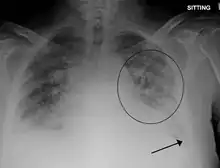

Pulmonary edema with small pleural effusions on both sides | |

Low oxygen saturation in blood and disturbed arterial blood gas readings support the proposed diagnosis by suggesting a pulmonary shunt. A chest X-ray will show fluid in the alveolar walls, Kerley B lines, increased vascular shadowing in a classical batwing peri-hilum pattern, upper lobe diversion (biased blood flow to the superior parts instead of inferior parts of the lung), and possibly pleural effusions. In contrast, patchy alveolar infiltrates are more typically associated with noncardiogenic edema[3]